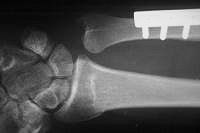

Late result: proper ulnar alignment restored.

The osteotomy and plate position are planned using a seven hole plate with a compression screw positioned obliquely across the osteotomy cut.

Late result - healed.